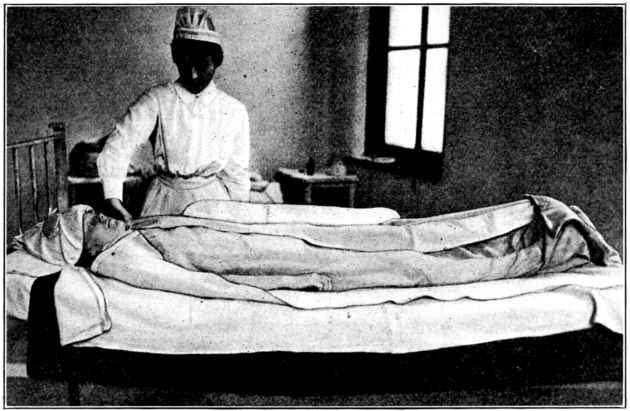

| 48. | Patient in hot pack given with dry blankets | 197 |